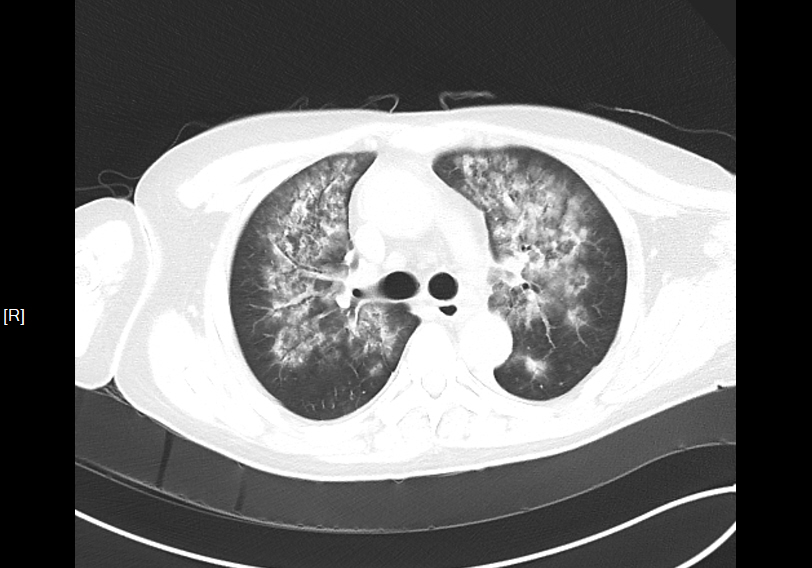

胸部 CT 显示 “两肺水肿”,双肾 B 超提示 “双肾回声增强、边界模糊”,进一步印证慢性肾损伤与心功能受累。

▲患者影像学检查